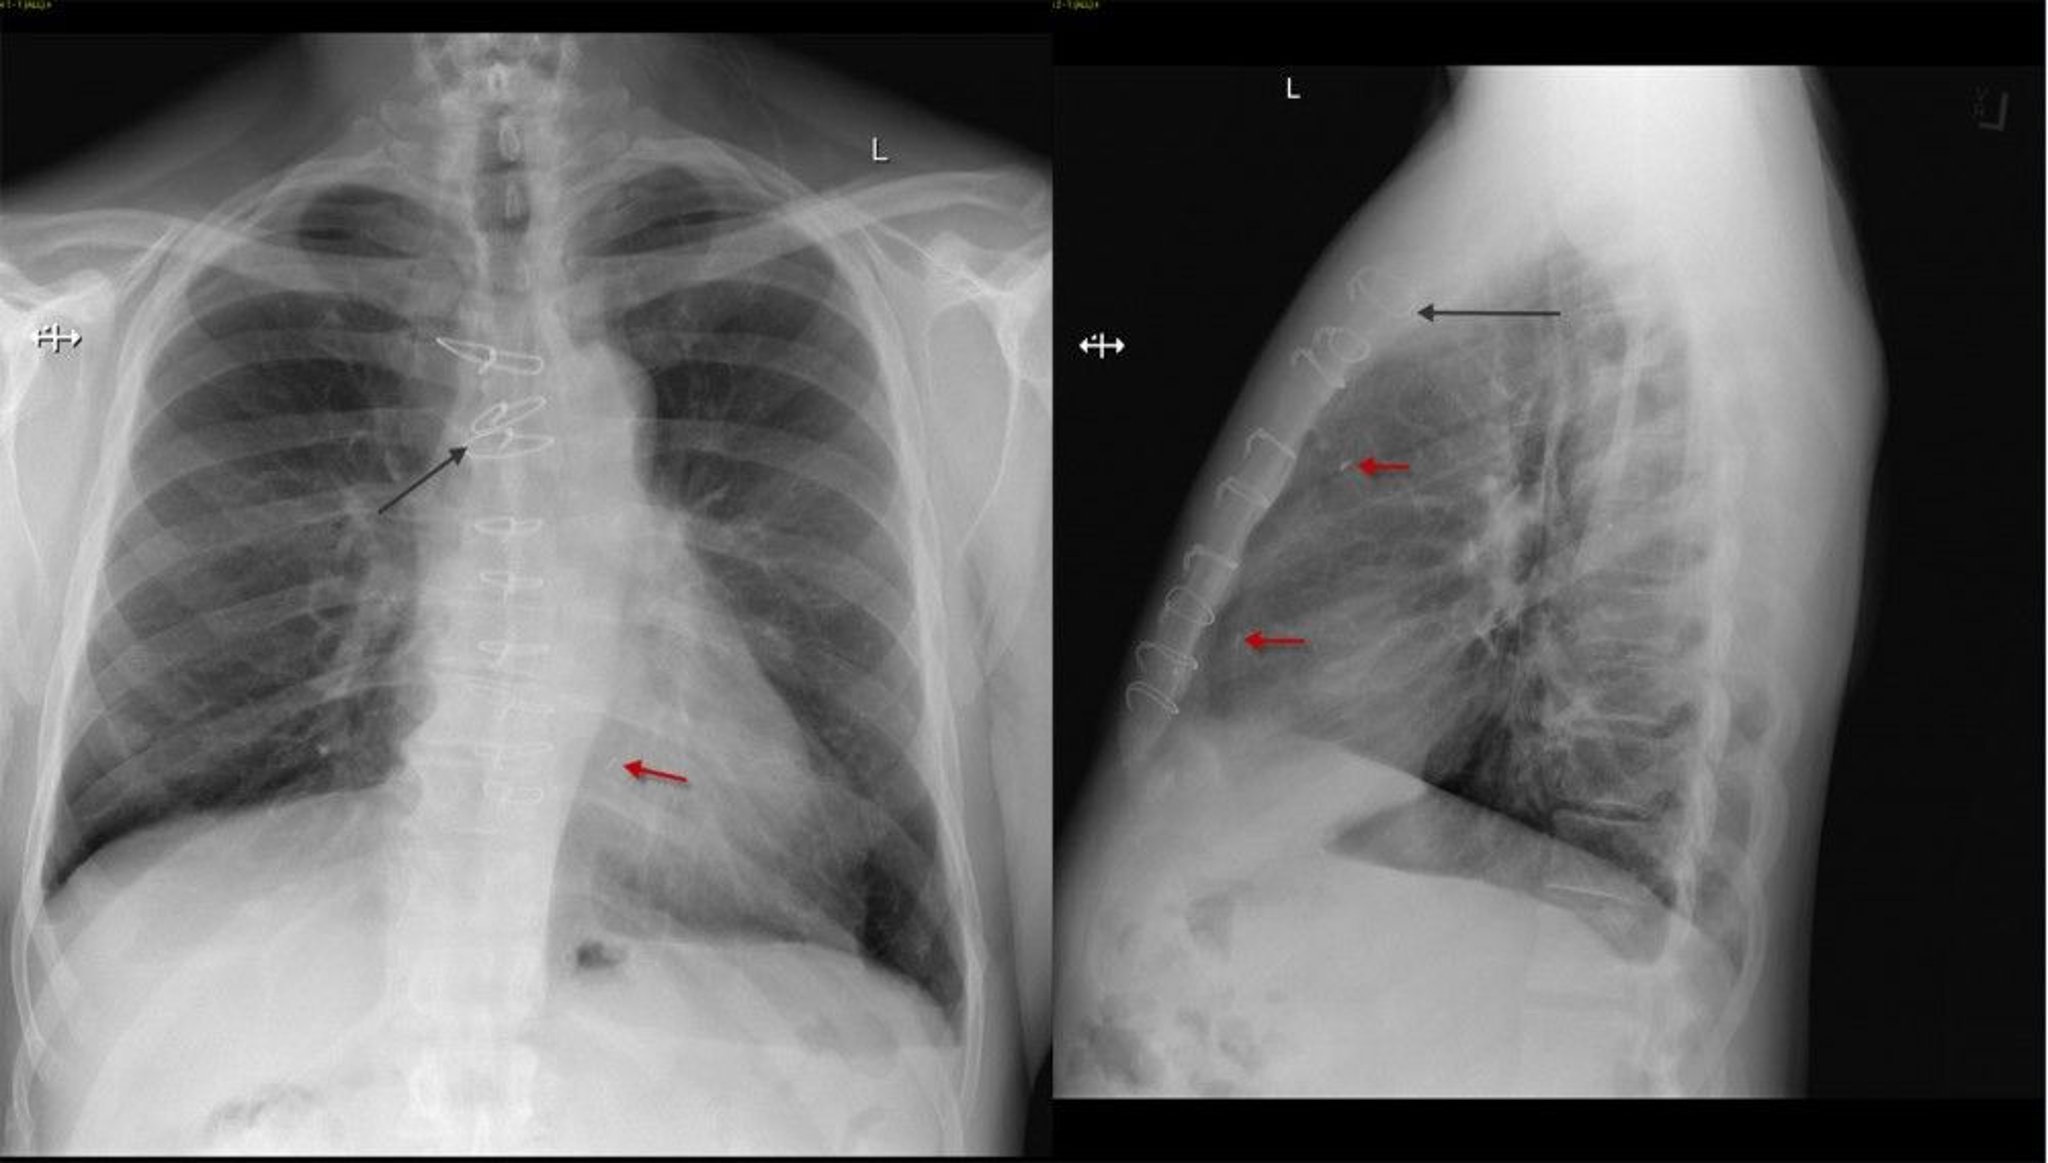

Рентгенограмма грудной клетки пациента после операции по шунтированию коронарной артерии

Фронтальная и латеральная проекции рентгенограммы грудной клетки пациента после операции аортокоронарного шунтирования, на которых видны грудинные швы (черная стрелка) и металлические скобы (красная стрелка).